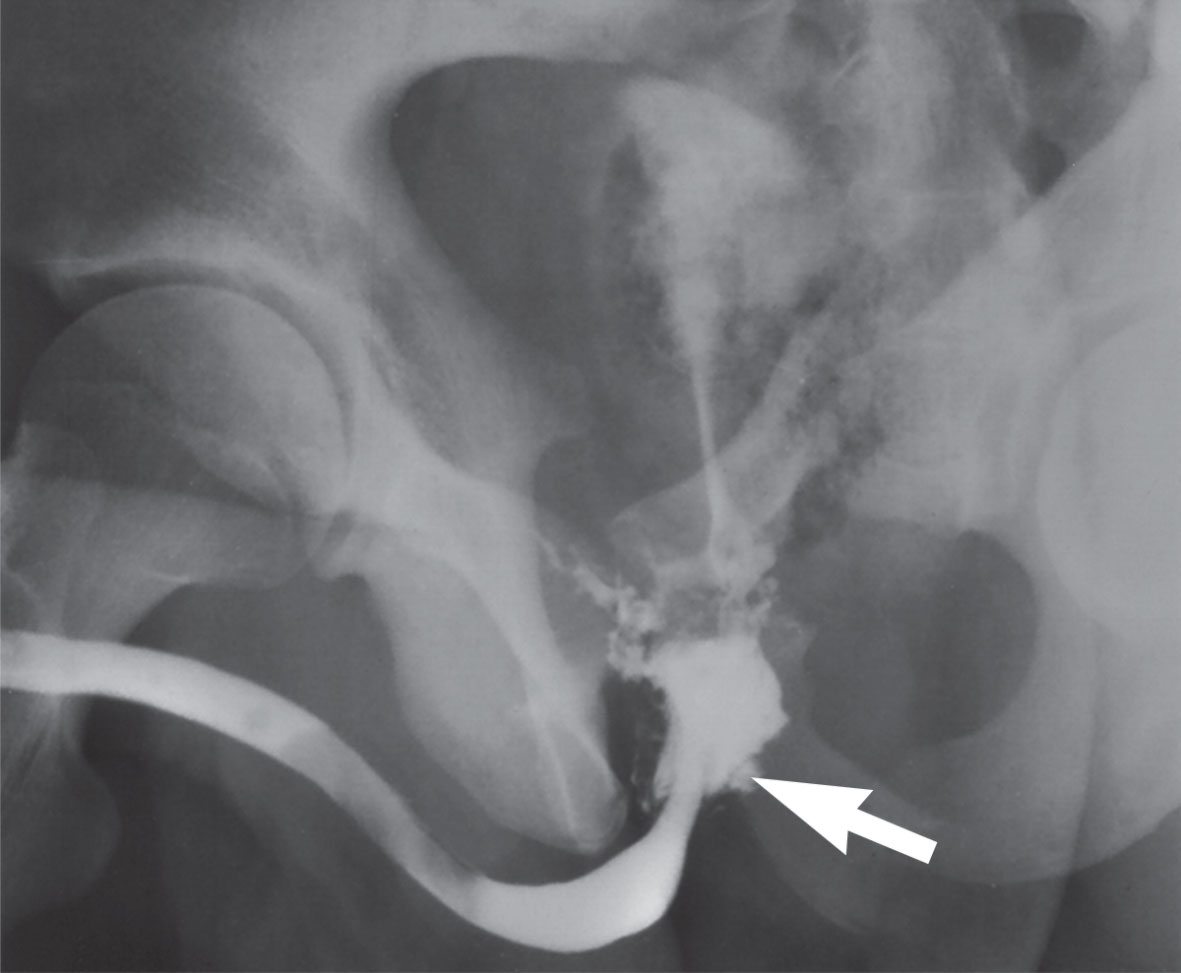

يظهر تمزق المثانة بتصويرها بعد إملائها بالمادة الظليلة ثم تصويرها بعد إفراغها عبر القثطرة، فتُشاهد المادة الظليلة داخل الصفاق (الشكل 6) وخارج الصفاق (الشكل 7)، وهي قد لا تُشاهد في طور إملاء المثانة.

الشكل (7) صورة مثانة بالطريق الراجع تظهر المادة الظليلة داخل الصفاق.  | الشكل (6) صورة مثانة بالطريق الراجع تظهر المادة الظليلة خارج الصفاق.  |